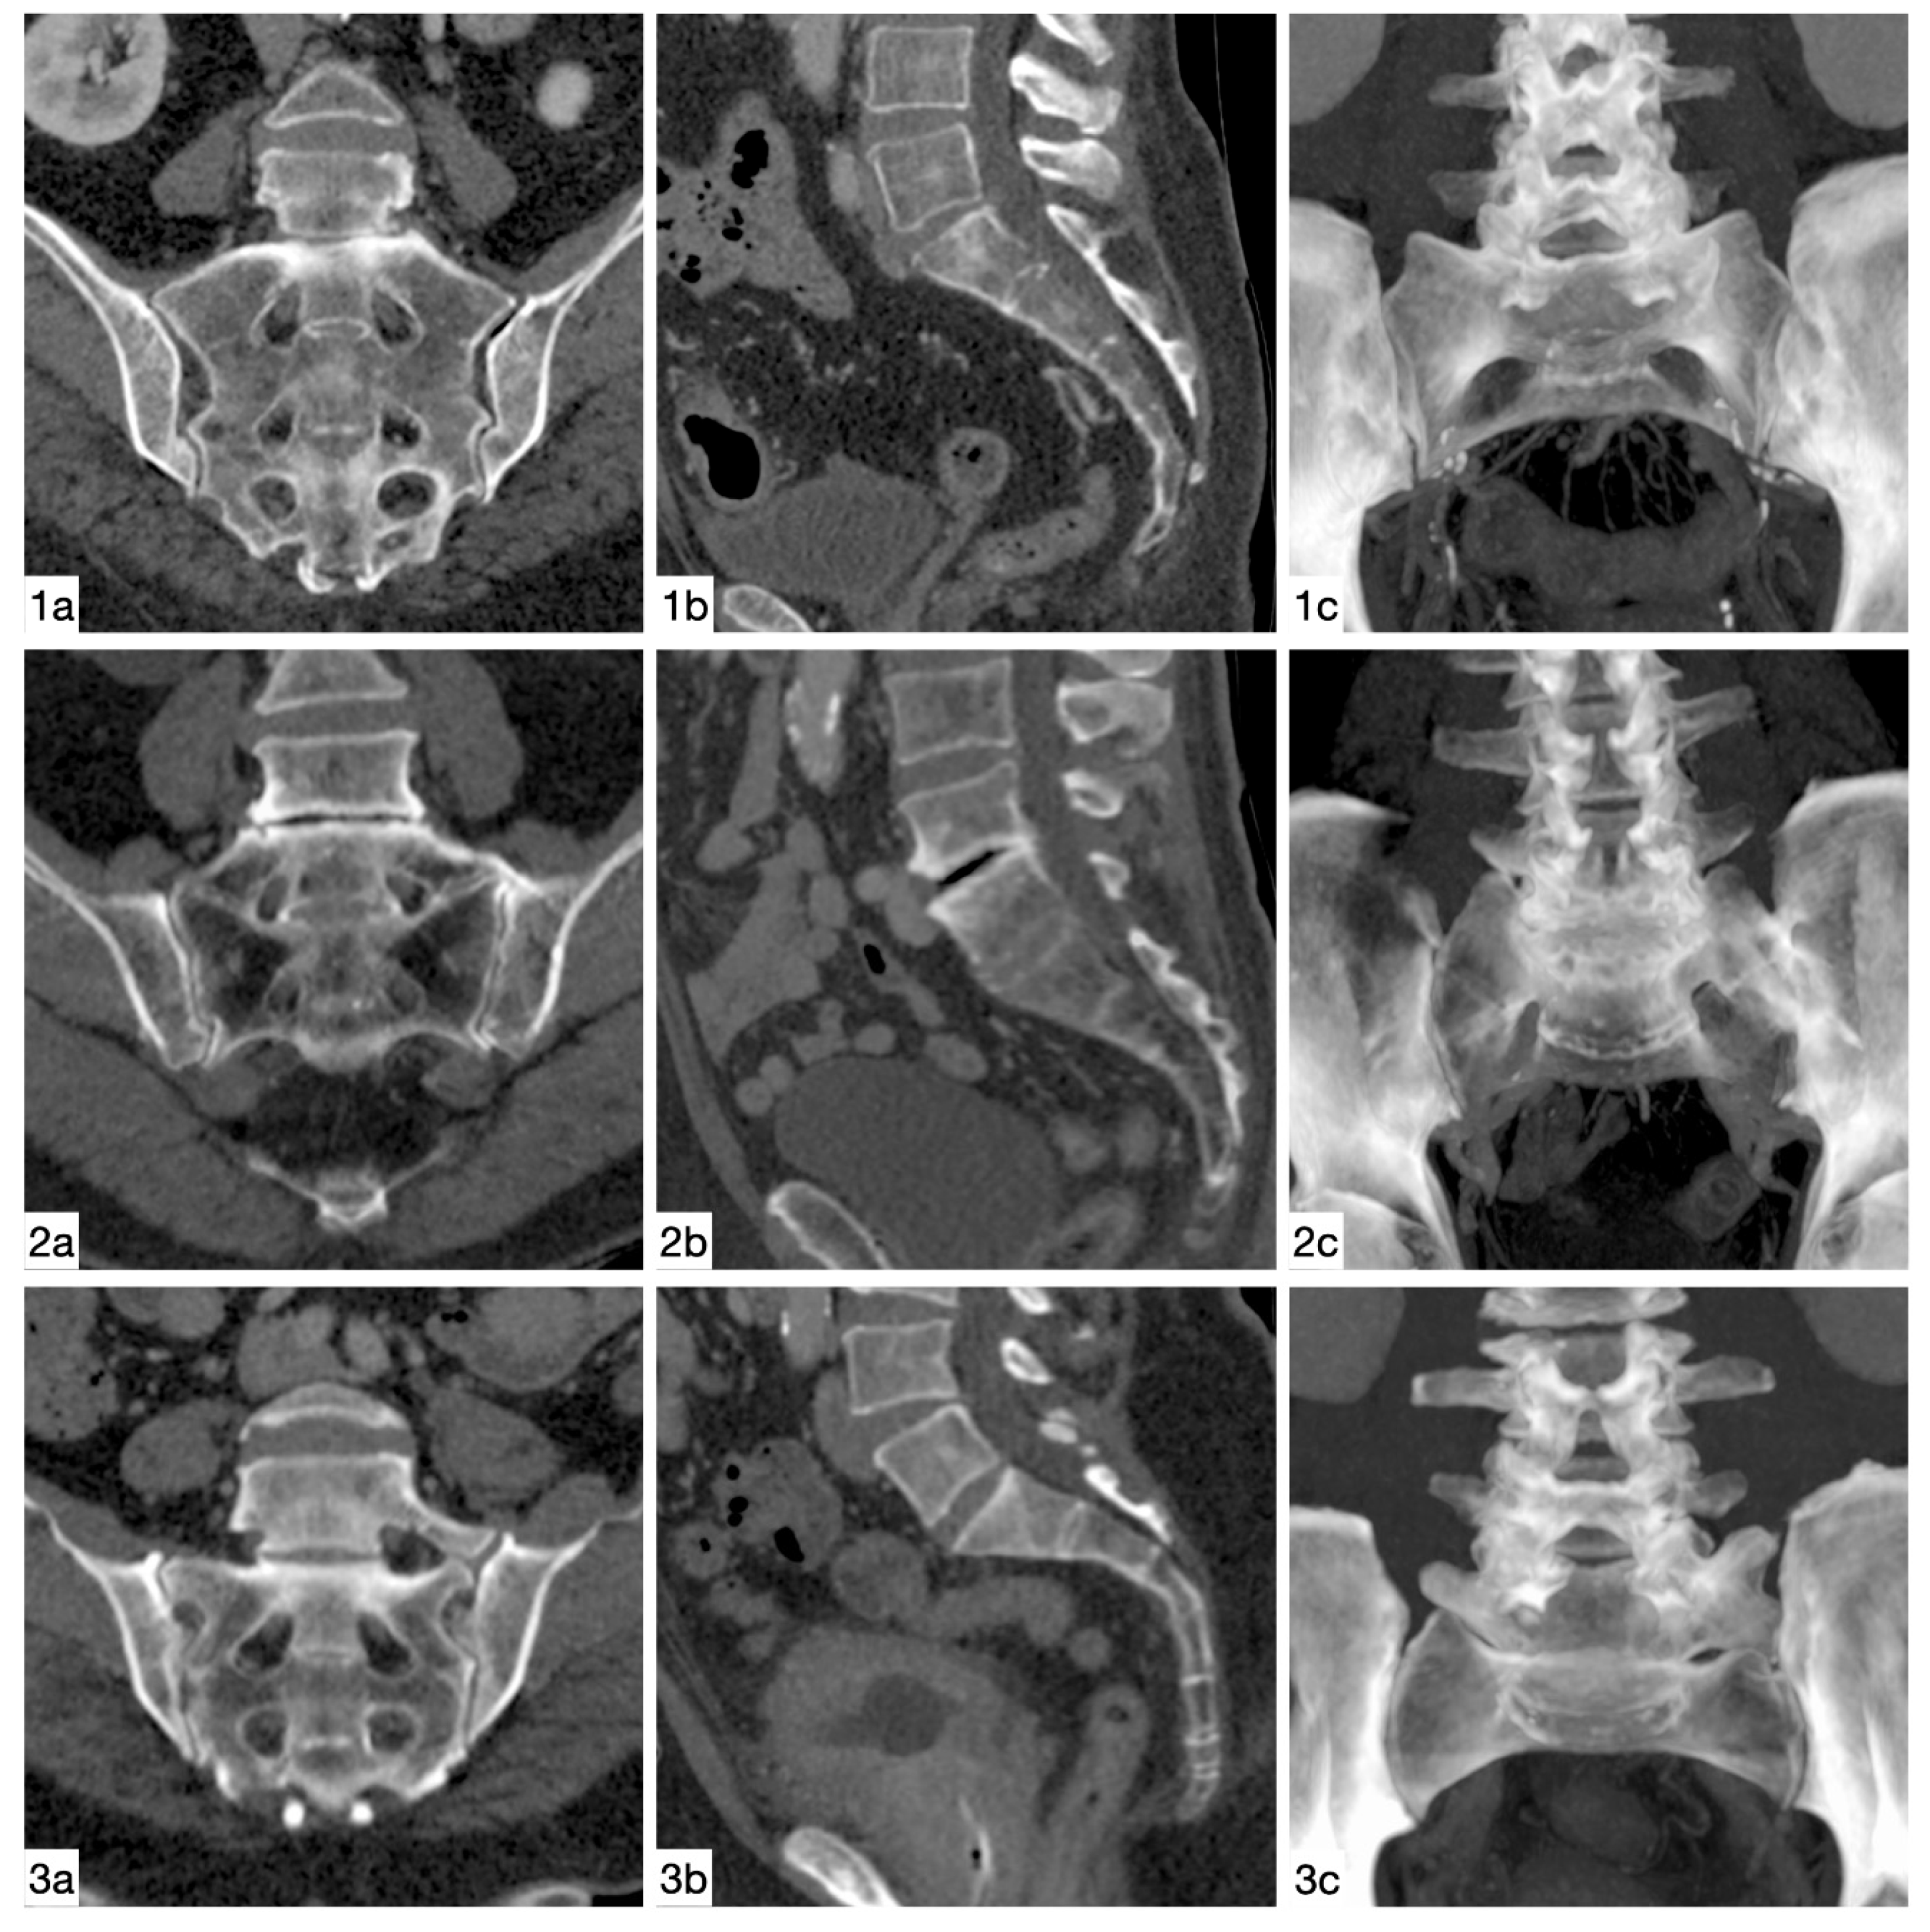

2. Materials and Methods

2.1. Individuals

2.2. Image Assessment